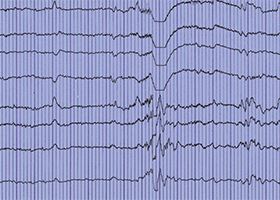

CARDIOVASCULAR TECHNOLOGY

NEURODIAGNOSTIC TECHNOLOGY

Earn an associate degree to enter this field or choose our specialization certificate to upgrade an existing credential